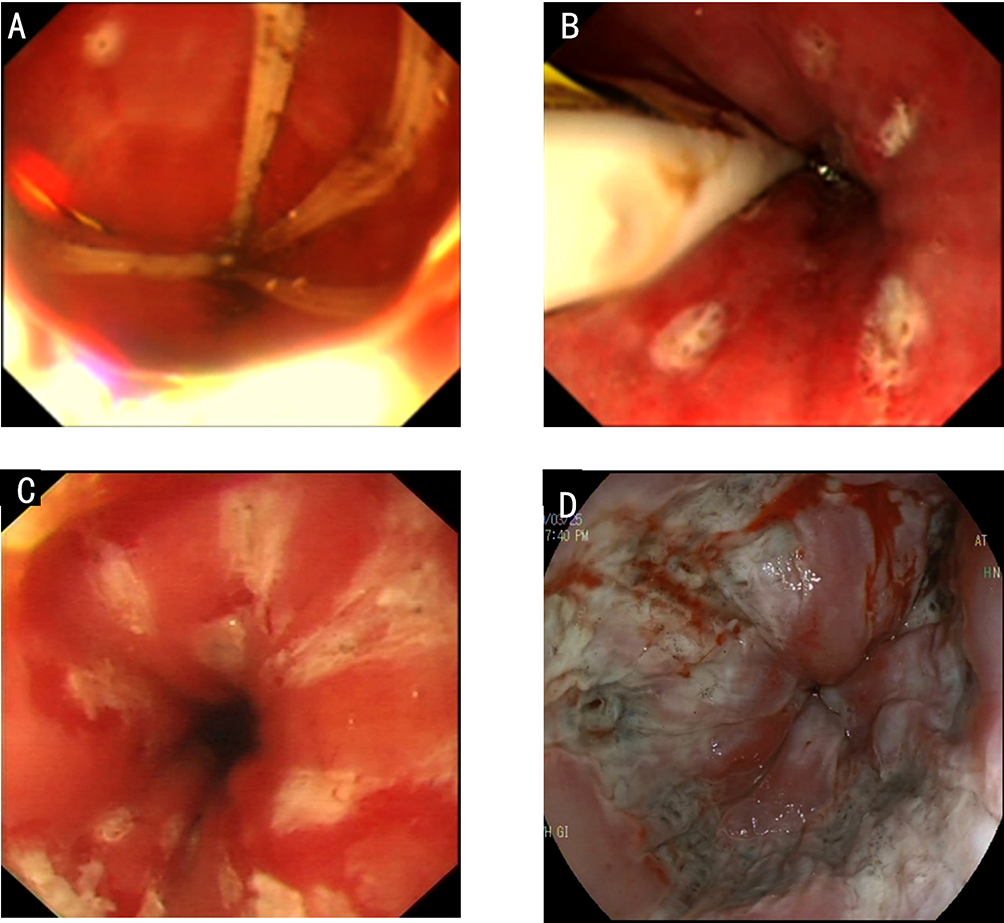

1. Peroral endoscopic myotomy (POEM). POEM has been widely used in the clinical treatment of achalasia; recently, applications in other parts of the human body have also been gradually emerging. In 2020, a study was conducted on a group of eight patients esophageal diverticulum and esophageal diverticulum treated by using POEM, also known as peroral diverticulum myotomy (D-POEM). D-POEM establishes a tunnel under the esophageal mucosa and incises the ridge between the diverticulum in the tunnel to make the diverticulum disappear. Postoperative follow-up of all patients, their preoperative symptoms were improved, and no adverse events were reported. Studies have shown that D-POEM has a certain effect on esophageal diverticulum, and that it is not affected by the position of the diverticulum and the length of the ridge between them, making it a safe and effective operation.

Gastric peroral endoscopic pyloromyotomy (G-POEM) is an operation creating a tunnel through the gastric antrum to dissect the pyloric muscle. Gastroparesis is a delay in gastric emptying due to insufficient gastric dynamics and reduced gastrointestinal peristalsis. Gastroparesis occurs after proximal gastric surgery such as cardiac cancer and is also a complication of diabetes. Hyperglycemia causes paralysis of the nervous system, thus triggering pylorospasm. By cutting down the spasmodic and constrictive pyloric muscle, G-POEM makes the pylorus loose its sealing function, and food can naturally flow into the intestine. So far, it has become a new treatment method for improving the symptoms of patients with refractory gastroparesis. A meta-analysis evaluated the clinical efficacy of G-POEM and pyloroplasty in the treatment of gastroparesis. The results showed that G-POEM is comparable to phaneroplasty in the treatment of refractory gastroparesis, but that it is significantly less invasive.